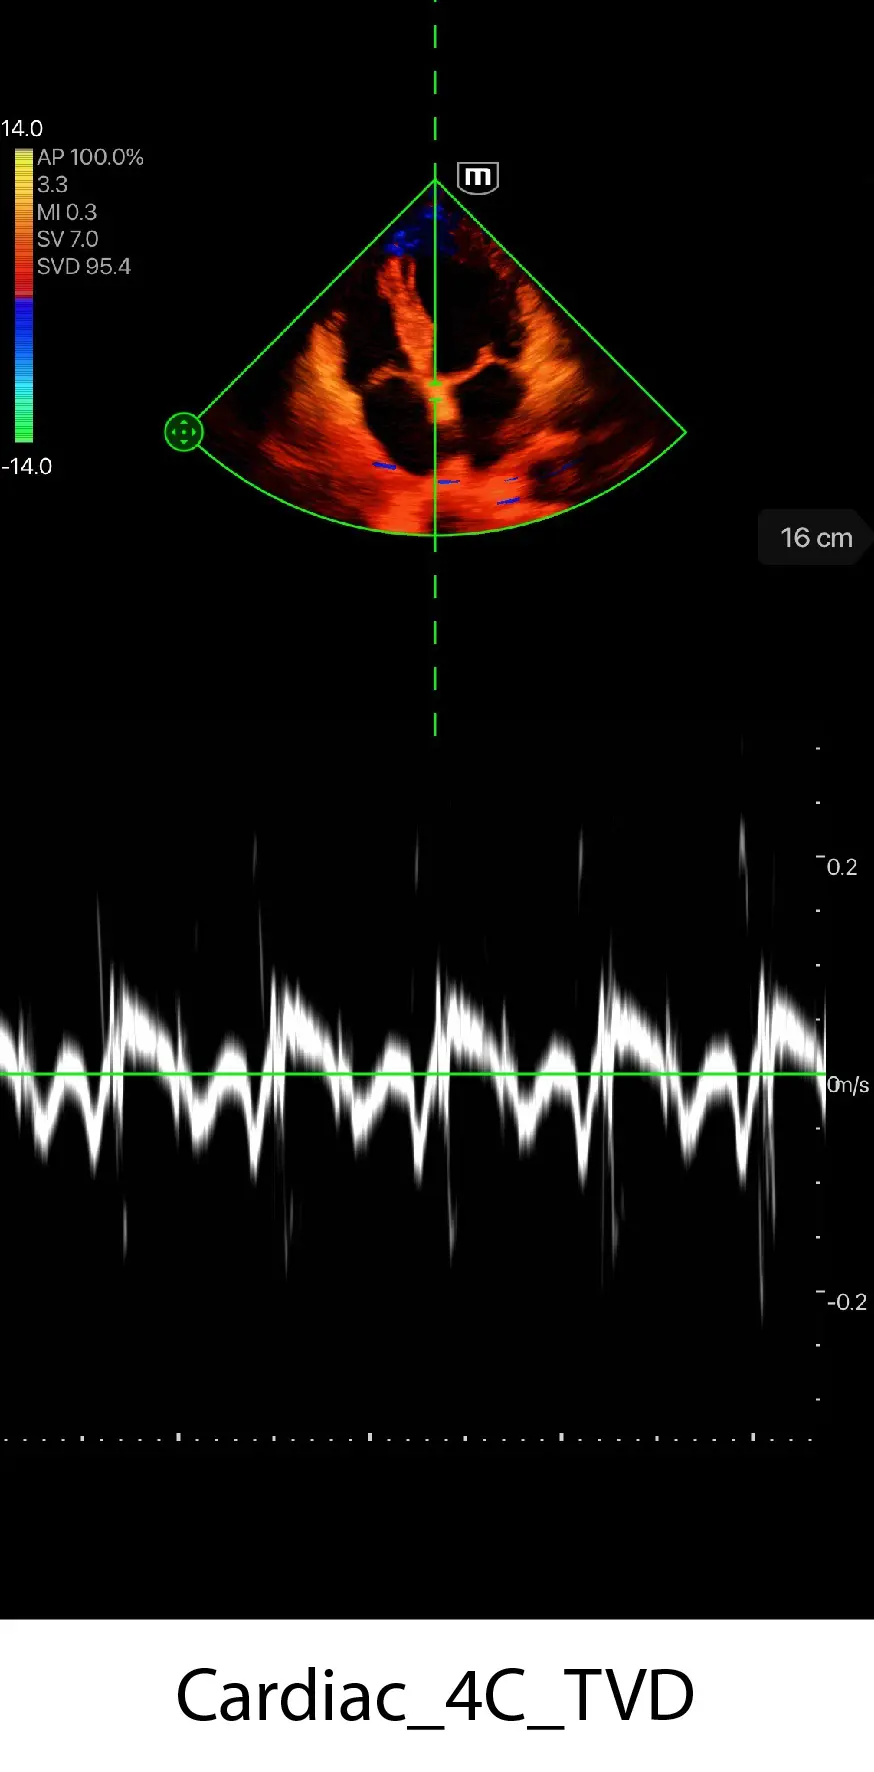

Клинични снимки